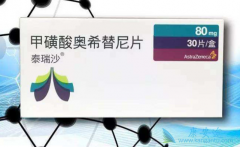

泰瑞沙 如此快速被批一线疗法的原因全靠去年在ESMO大会上公布的三期临床试验FLAURA的结果。在这个556名既往未接受过任何治疗的局部晚期或转移性EGFR突变阳性的非小细胞肺癌患者(60%以上都是亚裔)参加的三期大型双盲临床试验中,携带EGFR敏感突变的新 ...

我国每年新增肺癌病人约73万,居癌症死亡原因之首,其中非小细胞肺癌患者约占肺癌病例总数的85%,其中约30%―40%会发生 EGFR基因突变 。携带EGFR基因突变的患者对EGFR 酪氨酸激酶抑制剂 (tyrosine kinase inhibitors, TKIs)特别敏感,因此需要选择针对EG ...